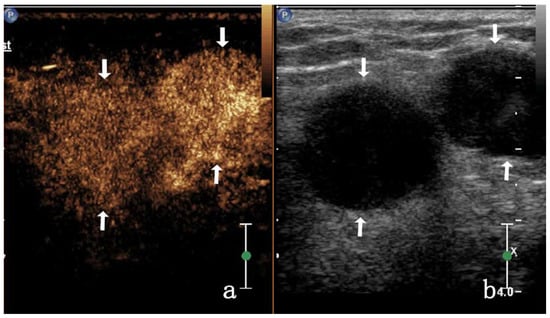

| Homogeneous enhancement | 3/17 (17.64%) | 23/28 (82.14%) | |||

| High enhancement | 8/17 (47.05%) | 28/28 (100%) | |||

| Centripetal enhancement | 0 | 16/28 (57.14%) | |||

| Noncentripetal enhancement | 17/17 (100%) | 12/28 (42.85%) | |||